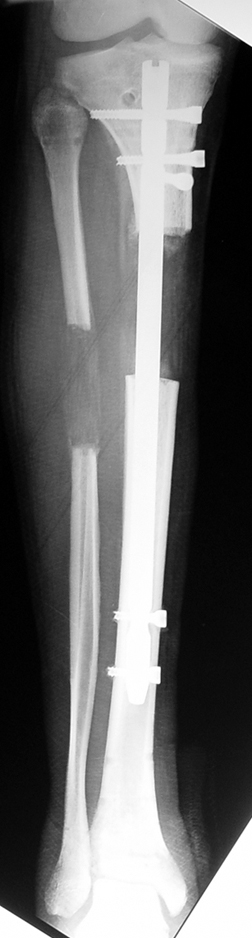

İntramedüller çivinin yerleştirilmesi ve osteotomi: Hasta traksiyon masasına supin pozisyonda yatırılır ve sağlam bacak altta olacak şekilde bacaklar makas pozisyonuna alınır. Standart yolla piriformis çukurundan medulla içine girilir ve kılavuz tel üzerinden kullanılacak çividen 1.5 mm daha kalın oyucu ile medulla oyulur. Proksimal femur, çivinin proksimali daha kalın olduğu için daha kalın oyulur. Radyografide osteotomi hattı planlaması yapılır. Planlama yapılırken uzatma sonunda distalde en az 8 cm. çivi kalması stabilizasyon için gereklidir. Kortikotomi perkütan olarak kortikotom ile tamamlanır. Daha sonra kılavuz tel çivinin boyunu ölçmek için distale ilerletilir. Uygun boyda intramedüller çivi çakılır. Son olarak çivi proksimalden kilitlenir ve bir adet dren konarak ameliyatın birinci kısmı tamamlanır.

Eksternal fiksatör uygulanımı: İntramedüller çiviye değmeden aşağıya ve yukarıya üçer adet Schanz vidası gönderilir. Vidalarla çivi arasında en az 1 mm den fazla mesafe olmalıdır.

Biz son zamanlarda, seçilmiş vakalarda, uzatma sonrası uzunluğu ve “alignment’ı” korumak amacı ile unilateral dinamik aksiyel fiksatör ve kilitli intramedüller çivi kombinasyonunu tercih etmekteyiz. Bu yöntemin ön şartları medullanın en dar çapının 7 mm.’den geniş olması ve uzatma sonrası distalde en az 8 cm. uzunluğunda çivi kalabilmesidir. İntramedüller çivi hem uzatma esnasında femurun üzerine gelen makaslama ve bükülme kuvvetlerini nötralize etmekte hem eksternal fiksasyon süresini kısaltmakta, hem de yeni oluşan kemiği kırıklara karşı korumaktadır. Serimizde bir vakada subtrokanterik femoral osteotomi yapılmıştır. İntramedüller çiviye rağmen varus angulasyonu oluşması yönünde bir dezavantaj tespit etmedik.

İlizarov, distraksiyon osteogenezisi için endosteal kan dolaşımının önemini vurgulamıştır. Biz tüm vakalarımızda femuru oyarak intramedüller çiviyi çaktık; buna rağmen hiçbir vakada kallus oluşma süresi tahminimizden daha uzun olmadı. Bu yüzden medüller dolaşımın bozulmasına bağlı yeni kemik oluşma hızında bir yavaşlama olmadığını düşünüyoruz. Oyma sonrası meydana gelen revaskülarizasyon, intramedüller çivili fiksasyon stabilitesi ve erken fonksiyonel yüklenme bu gerçeğin temelini oluşturmaktadır. Eksternal ve internal fiksasyon yöntemlerinin kombine kullanımının potansiyel dezavantajları kan kaybının artması, intramedüller infeksiyon, yağ embolisi olasılığı ve aşırı metal yüküdür. Bunların içinde en çok korkulan problem bir çivi dibi infeksiyonun tetikleyeceği derin intramedüller infeksiyondur (panosteomyelit). Bizim serimizde bu yönde hiçbir komplikasyon gelişmemiştir. Bu olası komplikasyonun önlenmesi amacı ile uzatma sonundaki kilitleme medialden yapılmalıdır; ayrıca intramedüller çivi ve eksternal fiksasyon pinlerinin teması önlenmelidir.